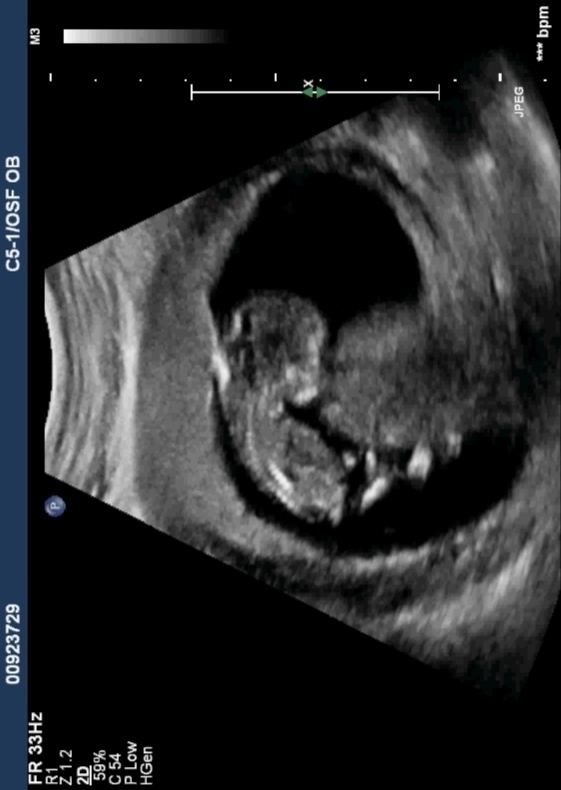

I know it is early and this isn't a great pic, but any thoughts on gender? I was 12 weeks, 1 day.

Yeah I wasn't given any good profile shots.:-/ Here's what I have...Attachment 12408Attachment 12409Attachment 12410

Since I can't see a nub I'd say girl

Sure let me try...Attachment 12423Attachment 12424Attachment 12425Attachment 12426